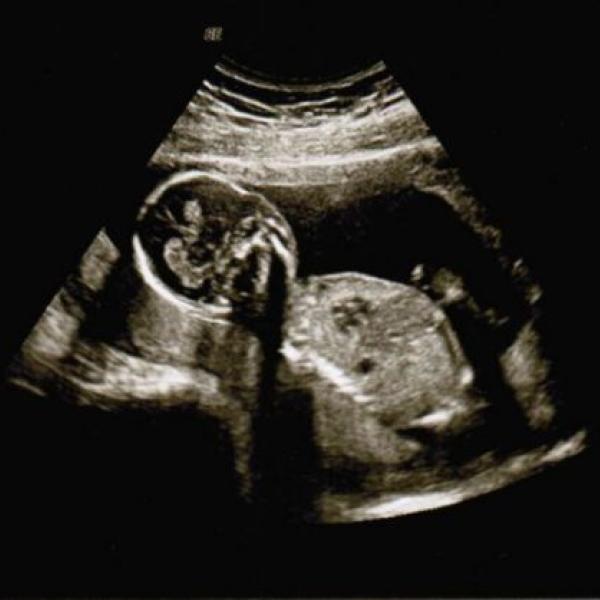

Oliva cerna 07.10.2011 Detail co myslíte, je to chlapeček? :) Komentáře jsou momentálně nedostupné. Děkujeme za pochopení. Oliva cerna 14.07.2011 Detail Dnešní první kontrola 4+6tt, zatím není moc vidět, přesto radost velikááá :) kontrolu máme za týden :) Komentáře jsou momentálně nedostupné. Děkujeme za pochopení.